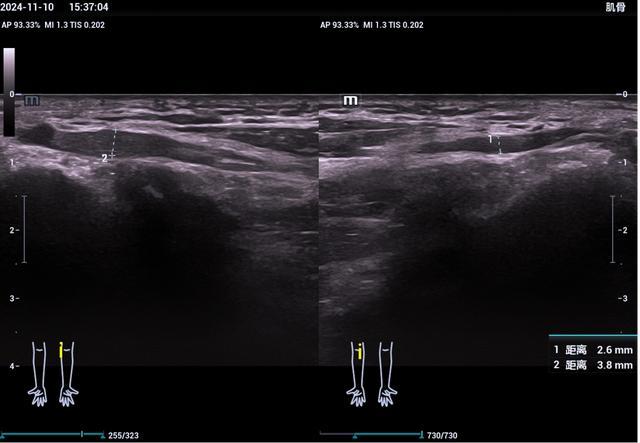

3、高分辨率

高频探头能清晰显示毫米级结构(如肌腱纤维、神经束),对浅表组织损伤尤其敏感。